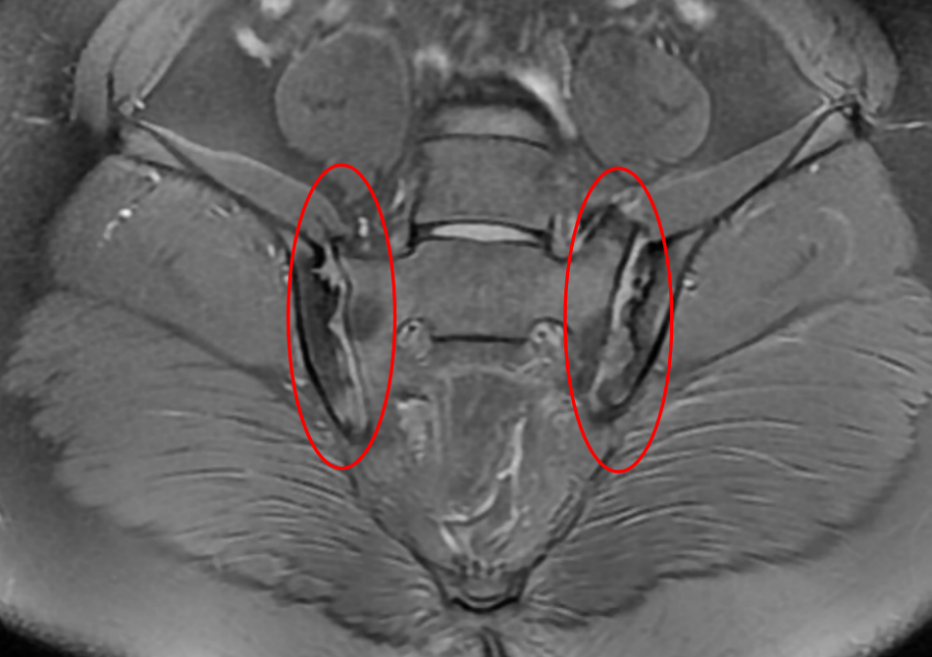

核磁共振提示骶髂关节炎

经过详细的问诊与全面的检查,发现潘潘存在骶髂关节炎症和髋关节炎症查了感染、肿瘤遗传代谢方面原因都无果追问病史发现患儿家里哥哥就是一位强直性脊柱炎患者再去查孩子的HLA-B27,显示结果阳性结合病史最终确诊为“幼年特发性关节炎”